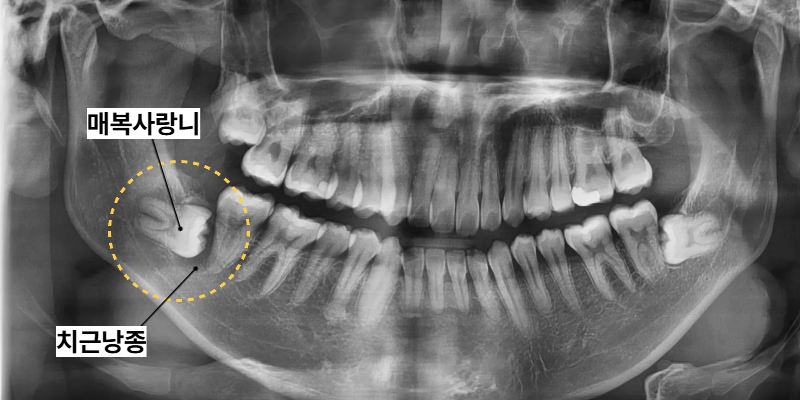

이번 동탄역치과 사례의 환자분은 30대 남성으로

하악 부위 매복사랑니와 물혹이

함께 발견되었습니다.

물혹이 자리를 잡고 있어서

2차적인 문제를 야기할 수 있으므로